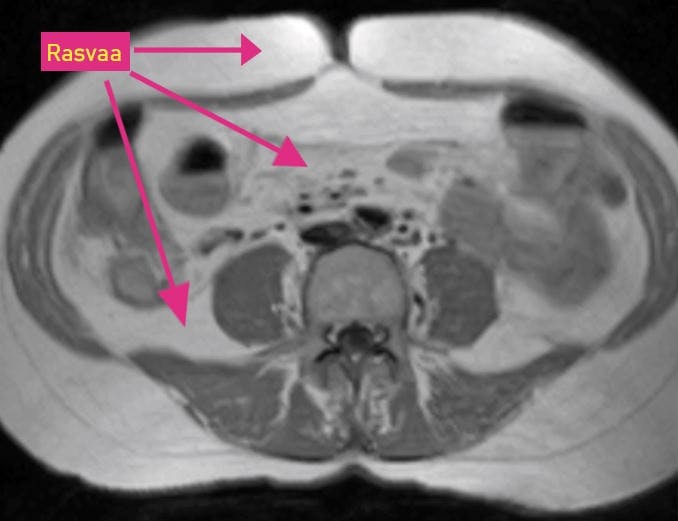

RASVAA VÄLITTÖMÄSTI IHON ALLA Vatsan poikkileikkaus. Kuvassa valkoisena näkyvää rasvaa on jonkin verran välittömästi ihon alla, mutta niukasti sisäelinten välissä.